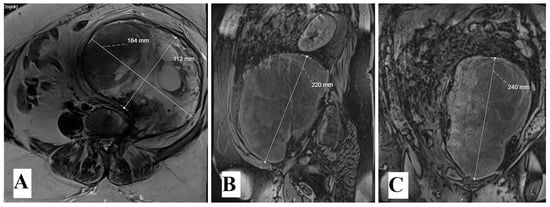

A Rare Case of a Gigantic Retroperitoneal Schwannoma

2. Case Report